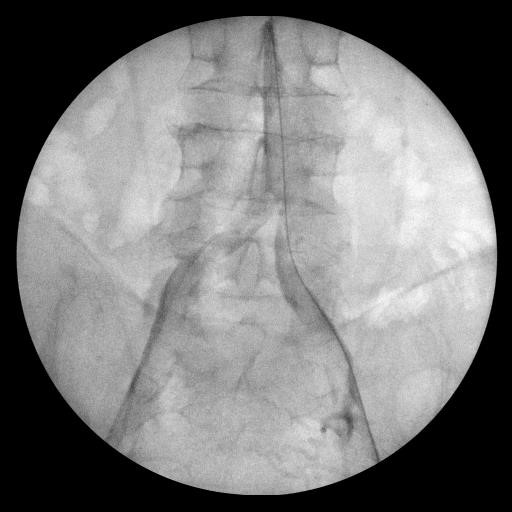

Пациент Ч.  МСКТ

•МСКТ аорты и артерий н/конечностей: КТ признаки окклюзии терминального отдела аорты и подвздошных артерий с обеих сторон.